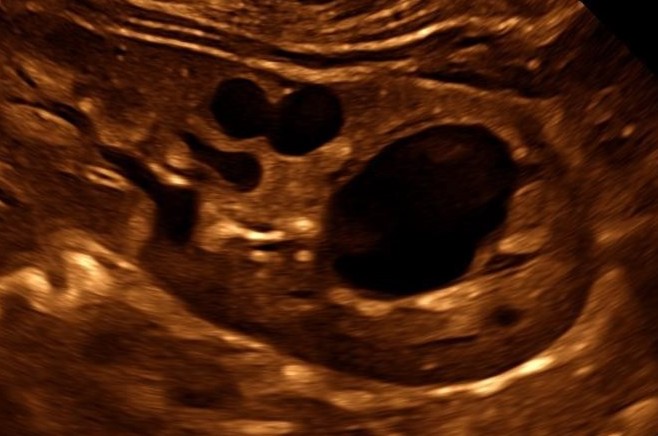

Viele zystische Nierenerkrankungen zeigen typische Veränderung in der Sonographie. Daneben ist die molekulargenetische Untersuchung zur Sicherung der Diagnose wichtig.